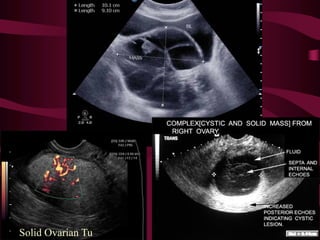

TVS: Features suggestive of malignancy

• Bilateral

• Fixed

• Variegated

consistency

• Solid

• Nodules in pouch of

Douglas

• Ascites -

Haemorrhagic

Solid Ovarian Tu

Bilateral: Cyst and mass in each ovary